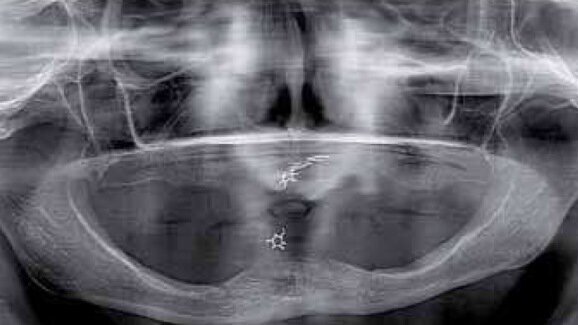

W fazie planowania leczenia wykonano badania OPG oraz CBCT. Badania uwidoczniły masywny zanik części zębodołowej wyrostka żuchwy do jej trzonu – klasa 3. Zanik ten nie wykluczał leczenia pacjentki, jednak eliminował żuchwę jako miejsce dawcze dla ewentualnych przeszczepów kości dla rehabilitacji szczeki. W szczęce uwidoczniono masywny zanik części zębodołowej wyrostka w odcinku przednim wraz ze zwiększeniem upowietrznienia zatok szczękowych i deformacją płaszczyzny powierzchni kości. Jest to obraz typowy dla pacjentów użytkujących przez lata protezy całkowite w szczęce przy współistniejącym uzębieniu resztkowym w odcinku międzybródkowym żuchwy. Taki stan nazywamy zespołem Kellego (Ryc. 1).

Taki stan jest ogromnym utrudnieniem dla leczenia protetycznego bezzębnej szczeki przez niekorzystną relację płaszczyzny pola podparcia protezy do płaszczyzny protetycznej. Znaczny stopień zaniku wyrostka w okolicy podnosowej eliminuje to miejsce z zabiegów GBR. Do rozważań pozostają zatem odcinki boczne w rzucie zatok szczękowych. W przypadku opisywanej pacjentki CBCT uwidoczniło zadowalający wymiar wertykalny przy ubytku horyzontalnym w postaci bagnetowatego szczytu wyrostka zębodołowego (Ryc. 2).

Po analizie CBCT z szablonem protetycznym zadecydowano o zastosowaniu metody augmentacji horyzontalnej z użyciem techniki śrub namiotowych w rzutach zatok szczękowych obustronnie. Jako materiał augmentacyjny postanowiono zastosować ksenograft (Bio-Oss) zmieszany z wiórami kości autogennej pobranej z otworów osteotomijnych w żuchwie.

Po kontroli dopasowania i kontroli okluzji uzupełnienie dokręcono z siłą 15 Ncm. Otwory śrub zamknięto kompozytem Luxaflow (DMG). Leczenie zostało zakończone (Ryc. 21-25). Efekt estetyczne w pełni zadowolił pacjentkę jak i zespół (Ryc. 26 i 27). Zlecono wizyty kontrolne co 6 miesięcy. Podczas kontroli przeprowadzonej 24 miesiące po oddaniu uzupełnień wykonano kontrolne CBCT, które ujawnia zadowalający stan podłoża kostnego (Ryc. 28-29).